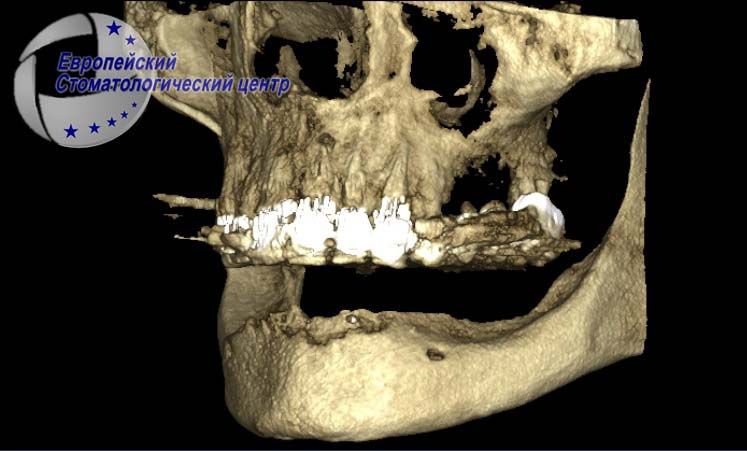

После установки имплантатов проводилась компьютерная томография с целью подтверждения правильности расположения имплантатов (рис. 2, 3).

Операция дентальной имплантации была спланирована виртуально в программе DDS-Pro по КТ, сканом моделей и wax-up. В дистальных отделах нижней челюсти были установлены винтовые одноэтапные имплантаты с кортикальной фиксацией в обход нижнечелюстного канала, а в переднем отделе проведена имплантация корневидными имплантатами с винтовой внутрикостной частью. Длина внутрикостной части всех имплантатов – 10 мм, толщина – 3,0 мм.

Таким образом, тщательное планирование хирургического вмешательства с проведением компьютерной томографии обеспечило отсутствие осложнений во время хирургического вмешательства в случае установки одноэтапных корневидных имплантатов: в боковом участке – в обход нижнечелюстного нерва, а в центральном участке – в лунки удаленных зубов.